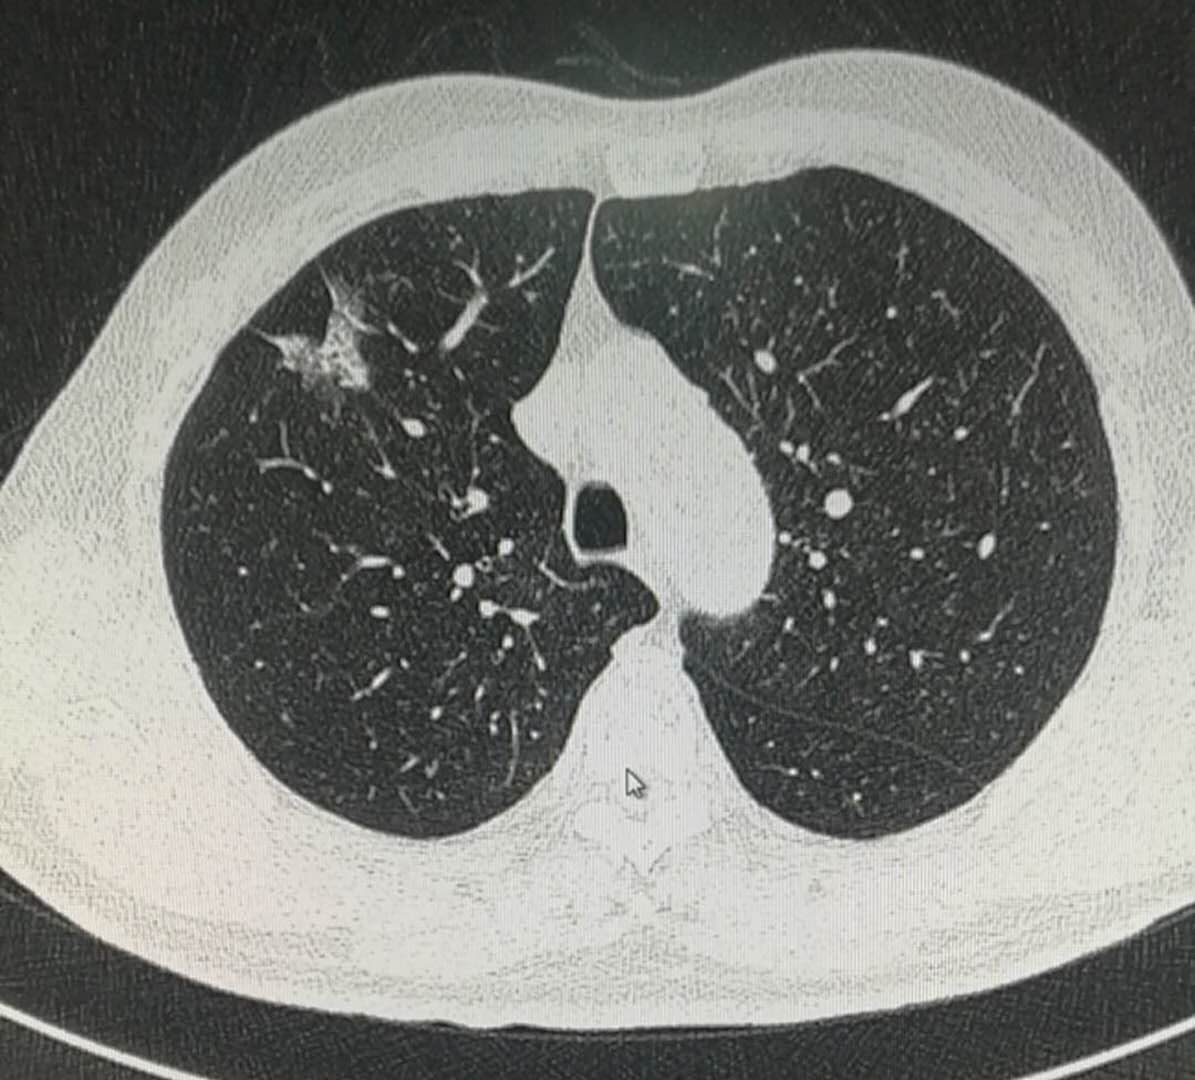

老爷子身板硬朗,没有任何不适症状,但是肺部CT发现了磨玻璃结节:

这个病灶位于右上肺叶,边界清晰,在磨纱玻璃密度内部还可以看到白色的实性密度区,所以属于混合磨玻璃密度结节;

同时还可以看到线样的胸膜牵拉:

很遗憾,不属于,他的病灶接近3厘米了,并且伴有较多实性成分和胸膜牵拉。

据统计,这种线样的胸膜牵拉,侵犯胸膜的几率大约是20%。